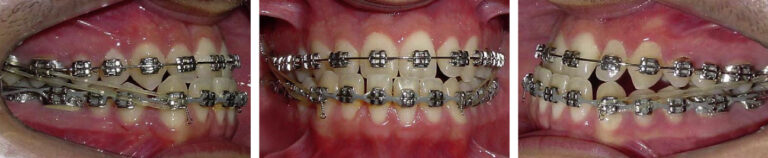

The patient was a man (age, 23 years 11 months) with a Class III subdivision left malocclusion with negative overjet and facial imbalance. His chief concerns were his anterior crossbite and lower lip protrusion. His parents had no Class III characteristics. The facial photographs showed a prognathic mandible and a Class III appearance (Fig 1). The patient could close his lips without mentalis strain, but he was self-conscious about the way his teeth occluded and the appearance of his teeth. The pretreatment intraoral photographs and dental casts show a Class III subdivision malocclusion with Class I on the right and Class III on the left (Figs 1 and 2). There was good alignment of the mandibular incisors, and all teeth were present including the third molars (Fig 3, A). Cephalometrically, he had maxillary retrusion, slight mandibular protrusion, and a balanced facial pattern, with the exception of excessive lower anterior face height. The maxillary incisors were bucally tipped and protruded, and the mandibular incisors were lingually tipped and retruded. He had an acute nasiolabial angle (Fig 3, B and C; Table).

Fig 1. Pretreatment facial and intraoral photographs.

Fig 2. Pretreatment dental casts.